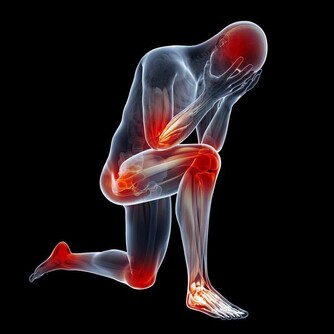

有一種口臭,跟口腔健康無關,而是身體其它部位發生問題而產生的氣味,通過口腔排出來而已。

不同氣味,暗示身體不同部位出問題。比如:

而尿騷味,則通常提示腎有問題了。

人體腎臟具有強大的代償功能,只要腎功能喪失不超過75%,仍能保持人體內環境的穩定。

所以,慢性腎衰病人早期常無明顯臨床症狀,往往容易誤診、漏診,使腎衰病人失去最佳的治療時機。